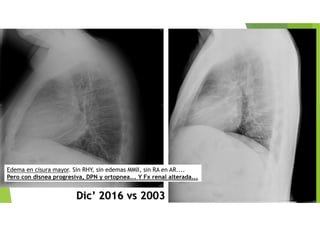

Dic’ 2016 vs 2003

Edema en cisura mayor. Sin RHY, sin edemas MMII, sin RA en AR....

Pero con disnea progresiva, DPN y ortopnea... Y Fx renal alterada...